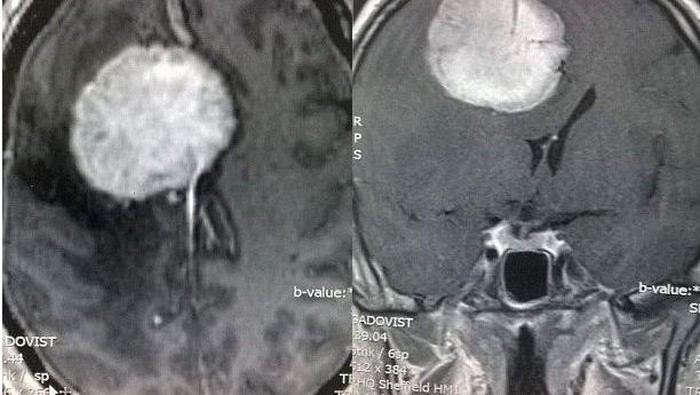

Ayah tiga anak ini lantas dibawa ke rumah sakit. Di sanalah ia diberitahu kabar yang mengejutkan, yaitu dengan ditemukannya tumor sebesar kepalan tangan di dalam otak Melvyn.

Rupanya untuk memastikan kondisi Melvyn setelah tertimpuk bola, dokter memutuskan untuk melakukan CT scan pada kepalanya. Namun mereka malah menemukan tumor.

Tak sampai tiga hari, Melvyn dirujuk ke Royal Hallamshire Hospital, Sheffield dan segera masuk ruang operasi. Tim bedah menghabiskan waktu hingga 12 jam untuk mengangkat seluruh tumor di otak Melvyn, yang untungnya masih tergolong jinak.